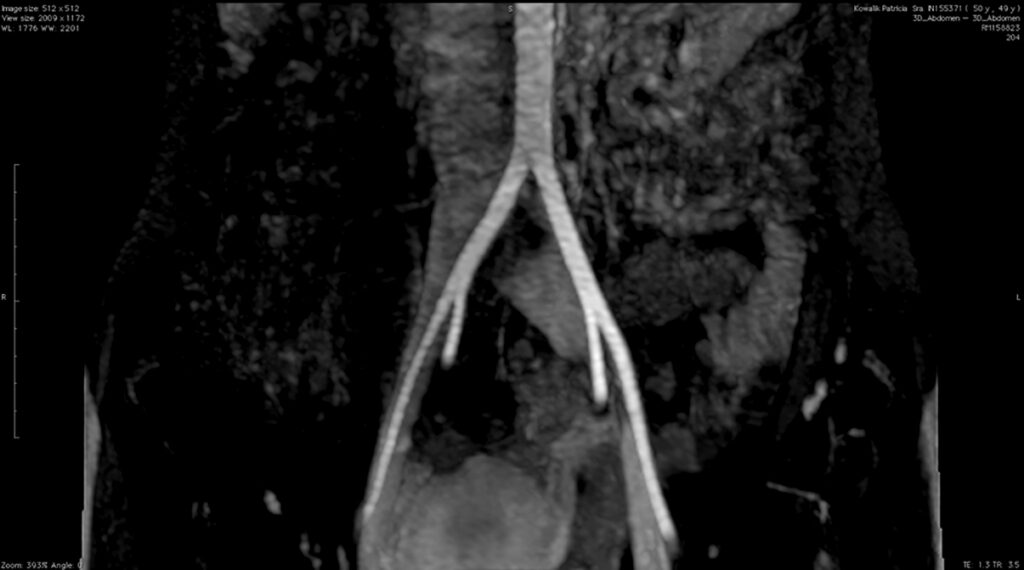

Fig. 8 y Fig. 9. AngioRM demostrando la dilatación de la VICI luego del pasaje entre AICD y la columna.

Se corrobora el diagnóstico presuntivo con flebografía y angioresonancia, observándose compresión de la VICI entre la columna y AICD y su dilatación distal (Fig. 8 y Fig. 9).